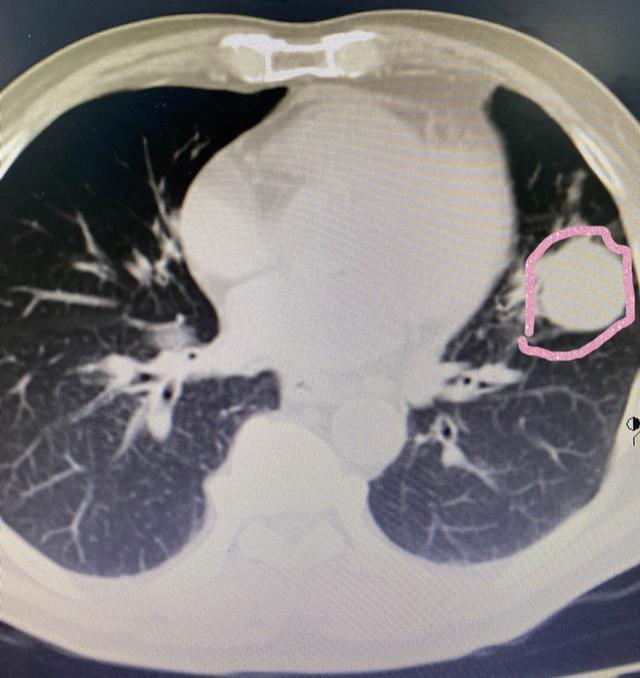

患者双肺典型多发转移灶,下图被我圈出来的是其中一个转移灶。

患者肺部肿块穿刺提示:间叶性来源、考虑恶性黑色素瘤肺转移,加做基因检测、支持病理诊断。